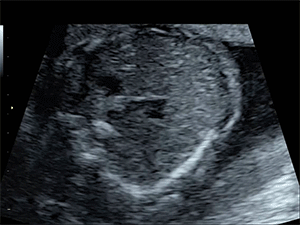

Fig 2b. Ultrasound videos of an abnormal heart. These kinds of videos were examined by doctors and the AI.